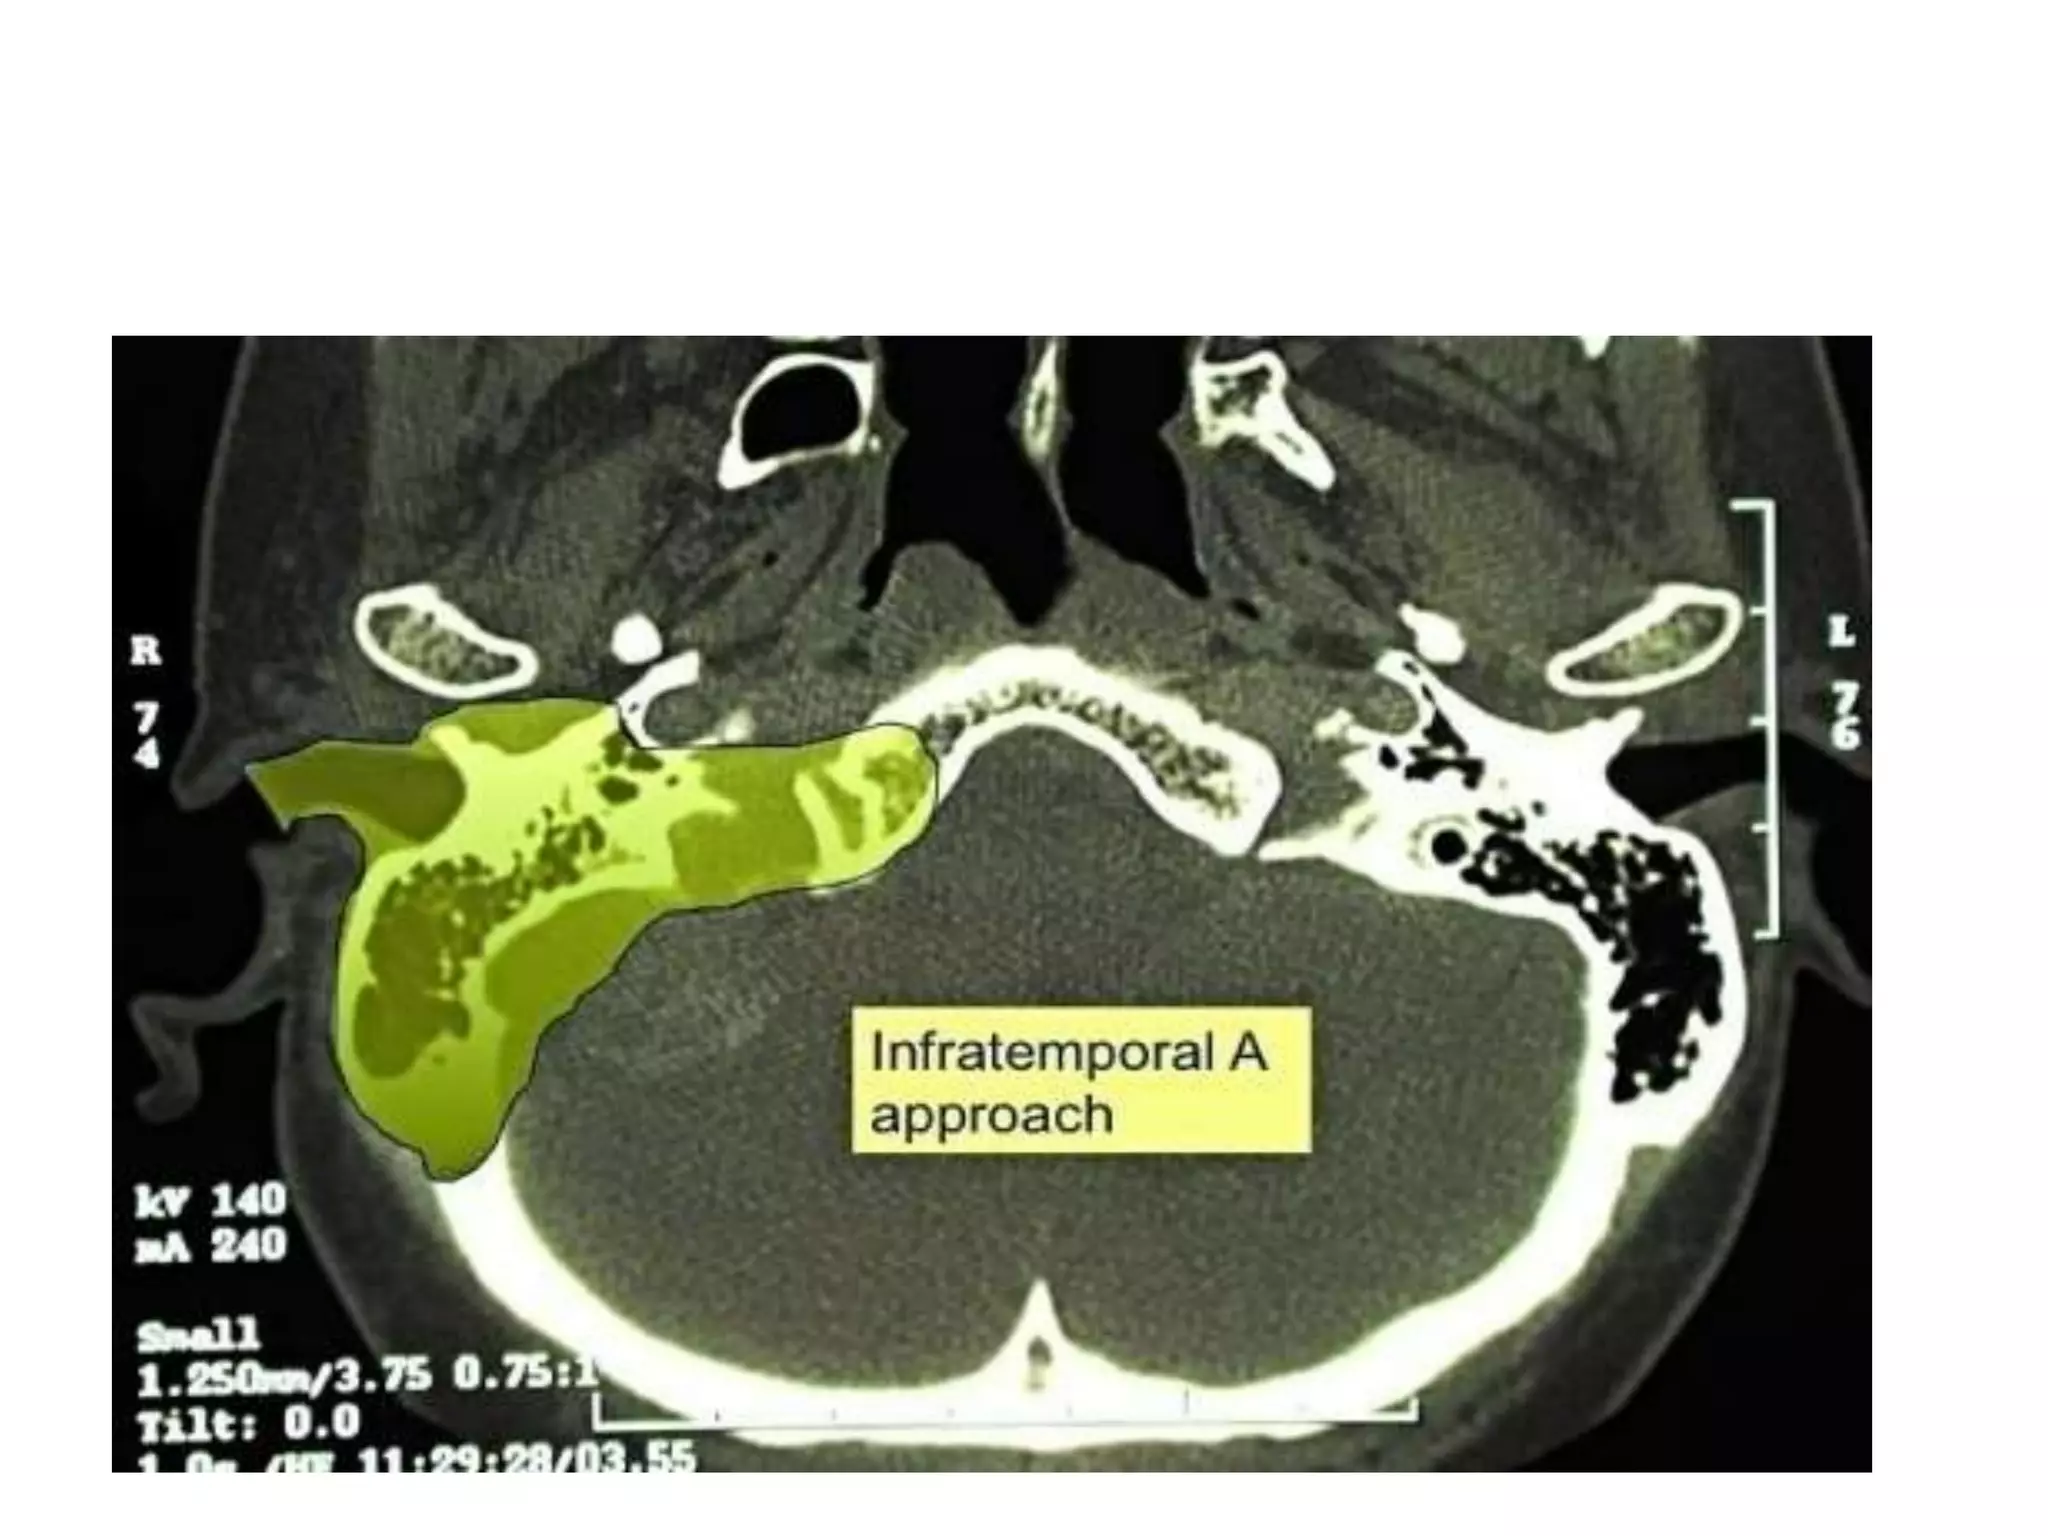

• Infratemporal approaches

• Approach that exposes the inferior aspect of

the temporal bone, with the jugular foramen

and the adjacent area of the parapharyngeal

space including the jugulo-carotid vessels .

• A large retroauricular and upper neck incision

opens the entry area. The dissection of the upper

neck exposes the jugular vein and carotid artery.

Removal of the outer ear canal and anterior

transposition of the VII cranial nerve allow drill

out removal of the infralabyrinthine petrous bone

up to the entire jugular foramen, to the occipital

condyle and low clivus.

• This typical skull base approach allows removal

of lesions from the CPA to the jugular foramen

and parapharyngeal space.